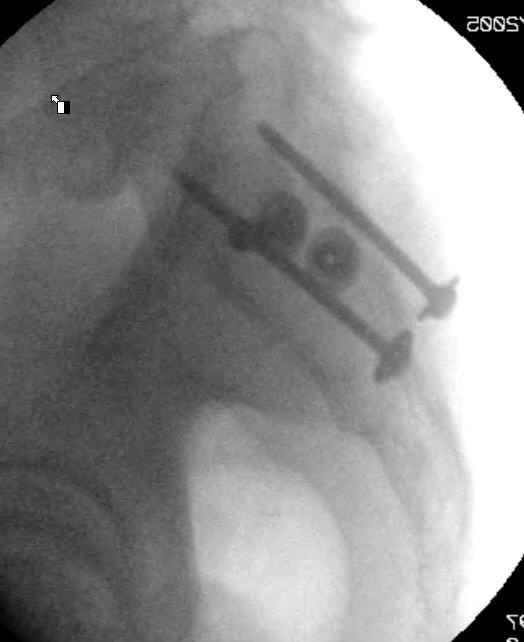

Hello gentlemen- Case is 52 YO male, fell out of treestand while deerhunting. He is 6 ft, approx. 260-275 lbs. Was hemodynamic unstable at local ER, sent to our Trauma center where circumferential pelvic binder placed and pt. stabilized with fluid, blood, and rewarming. Angiography not performed. An extraperitoneal bladder disruption was found, uro elected to treat non-operatively. Initial xray (not shown) demonstrated 5-7 cm wide at symphysis and SI joint. The first image attached is of CT once binder is in place. On post trauma day 5 the pt was taken to OR for ORIF of his iliac wing fracture and SI dislocation. The swelling/3rd spacing of fluid in the area of symphysis was profound, but quite acceptable posteriorly. Patient was prone for procedure, as I thought too difficult to fix the wing in lateral position. Of course the repair of wing was easy, but reduction of SI very demanding. The Floro images document the residual lack of reduction. That was the closest I could get it using 6mm joystick in wing, and clamp on sacrum and clamp through notch. The fixation was (initially) rigid. Anterior ex fix with supra-acetabular pins was placed due to condition of soft tissues, massive "beer-belly" overhanging the crest. Post trauma day ten patient's xray shows failure of posterior construct. Plan was to perform revision orif once soft tissues resolve considerably for full anrterior fixation and posterior fixation. However, while Im away for holiday (on Post trauma day 15), pt is developing septic clinical appearance, and trauma suspects pelvic abcess near symphysis and performs I and D - finds nothing but no primary closure performed. Posterior tissues/incision continue to look healthy. Now is post trauma day 17, pt is still tubed/on dopamine/and wbc still elevated, anterior incision still packed open. Clearly must get to bottom of possible sepsis, but then what? Thanks for you time - sorry for such lengthy clinical description. Thomas Schaller Kalamazoo, Michigan

5. Your caudal iliosacral screw is/was in his spinal canal... it's low and posterior and the lateral fluoro image confirms this... a postop CT will show it (or it's trail at this point)... canal screws do not hold.

6. Frames (even fancy new-style low ones) have poor mechanical stability when compared to symphyseal internal fixation...unstable rings in fat (and skinny) folks demand stable anterior and posterior stabilities... a frame

can't get you there... consider it a helper/support at best.